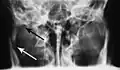

Plain film radiography

Traditionally, plain films of the mandible would be exposed but had lower sensitivity and specificity owing to overlap of structures. Views included AP (for parasymphsis), lateral oblique (body, ramus, angle, coronoid process) and Towne's (condyle) views. Condylar fractures can be especially difficult to identify, depending on the direction of condylar displacement or dislocation so multiple views of it are usually examined with two views at perpendicular angles.[11]

Towne's view of a bilateral condyle fracture. White arrow is a fracture on the neck of the condyle. Black arrow shows the condyle pulled to the medial. The same injury can be seen on the opposite side -